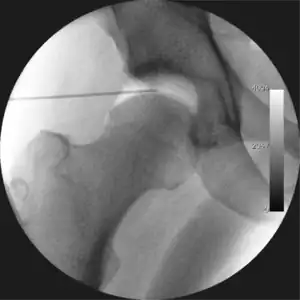

![]() Intraoperative fluoroscopic image during an arthroscopic resection of a cam lesion of the femur. The upper instrument is the arthroscope (viewing device), while the lower is the high-speed burr used for reshaping the bone. |

Standard arthroscopic treatment of symptomatic cam FAI involves debridement (resection) or repair of any labral [10] and chondral injuries [11] in the central compartment of the hip, and subsequent reshaping of the head-neck junction of the upper femur (osteochondroplasty) in the peripheral compartment [12][13] using high-speed motorised burrs that are similar in design to a dentist's drill (see fig. 9).